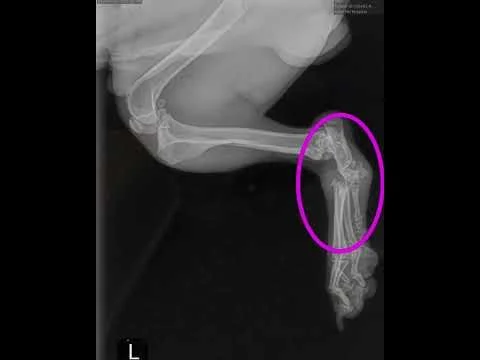

Roo showed signs of congenital birth defects in her legs (not surprising, given her rough start). Three of her legs were “good enough” for mobility, while the 4th leg was pretty messed up. We decided to do a series of surgeries to realign the bones on the worst leg. She is fully recovered and gets around pretty good (although, not sure that she could take long walks - maybe a stroller is in her future?)

We pulled Sage from the Stockton Shelter over a year and a half ago. She was just 3 months old and had been hit by a car. Both hips were in very bad shape. The side that took the impact was not salvageable (and the decision was to amputate that leg). The other side wasn't much better, but our vet thought that because she was young, the hip may "heal" enough on its own to be usable - and it appears that it did - because she definitely uses that leg like nothing ever happened. One of the families that nursed her back to health decided that they wanted to adopt her. Unfortunately, we probably "dropped the ball" on her adoption. We were so thrilled to find a home for a disabled dog, that we didn't focus enough on her breed - a working/herding Australian Shepherd (no matter how many legs she has). In hindsight, the family that adopted her wasn't the best fit for her needs, and they rightfully returned her.

Rupert came to us from the Sacramento County with an injured rear leg (probably from being hit by a car). X-rays indicated that his left rear ankle had been shattered. There were 2 options: amputation of the leg or an expensive arthrodesis surgery. We were fortunate to find a vet that was willing to offer us a discount on the repair surgery so that we could save his leg.